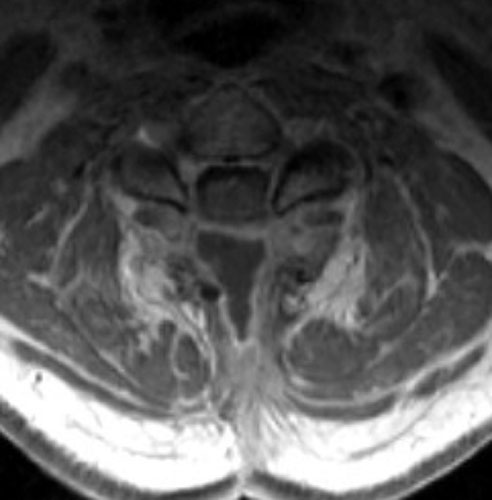

Seroma and Epidural Scar

C D